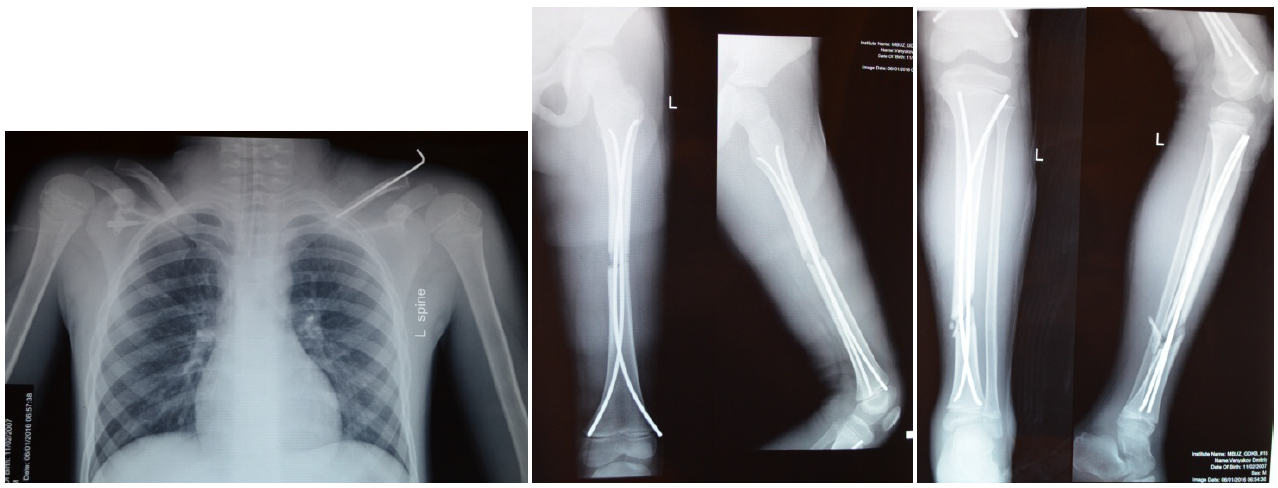

Клиника принимала на себя больных, которым оказывали первичную помощь на местах, включая хирургические вмешательства. Срок поступления в отделение нередко определялся состоянием больного и характером повреждений, отдаленностью места происшествия от краевого центра. Так, под нашим наблюдением был больной З., 11 лет, который был оперирован при поступлении в 1-е сутки по месту жительства на 2 сегментах (рис. 1).

Рис. 1. Больной З., 11 лет. Рентгенограммы после открытого остеосинтеза пластиной большеберцовой кости, внеочагового остеосинтеза бедра с целью транспортировки

У ребенка сохранялось грубое смещение полифрагментарного перелома бедра после наружного остеосинтеза, однако создание покоя для конечности дало возможность транспортировать больного в краевой центр для следующего этапа операции. При поступлении больного в клинику через 12 дней после ДТП и нормализации вегетативных функций осуществили повторную операцию. Вмешательство проведено закрыто, фиксация эластичными стержнями. Наступила консолидация в обычные сроки (рис. 2). Пластина и стержни удалены одновременно через полгода после травмы. Двойной уровень перелома и длительно не устраненное смещение на результат не повлияли.

Рис. 2. Рентгенограммы больного З. после консолидации спустя четыре месяца со времени операции. Видны следы костной мозоли, обозначающие контуры среднего фрагмента, полностью разобщенного в месте перелома в период травмы после бамперного удара